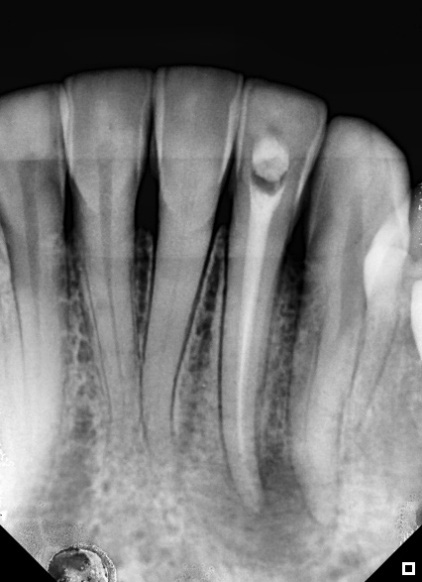

As with the first session, any remaining sodium hypochlorite was irrigated with saline solution. The canal was dried using absorbent paper cones and aspirator tips. The gutta-percha cone was selected (Figure 4) and obturation was realized with Bio-C Sealer (Angelus) (Figure 5A and 5B). A follow-up with 90 days was done and showed healing at the apical area (Figure 6A and 6B).

Figure 4: Guta-percha cone test